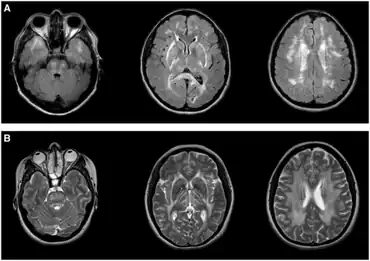

Leukoencephalopathies in adults-a) Typical imaging appearance of CADASIL b) CARASAL